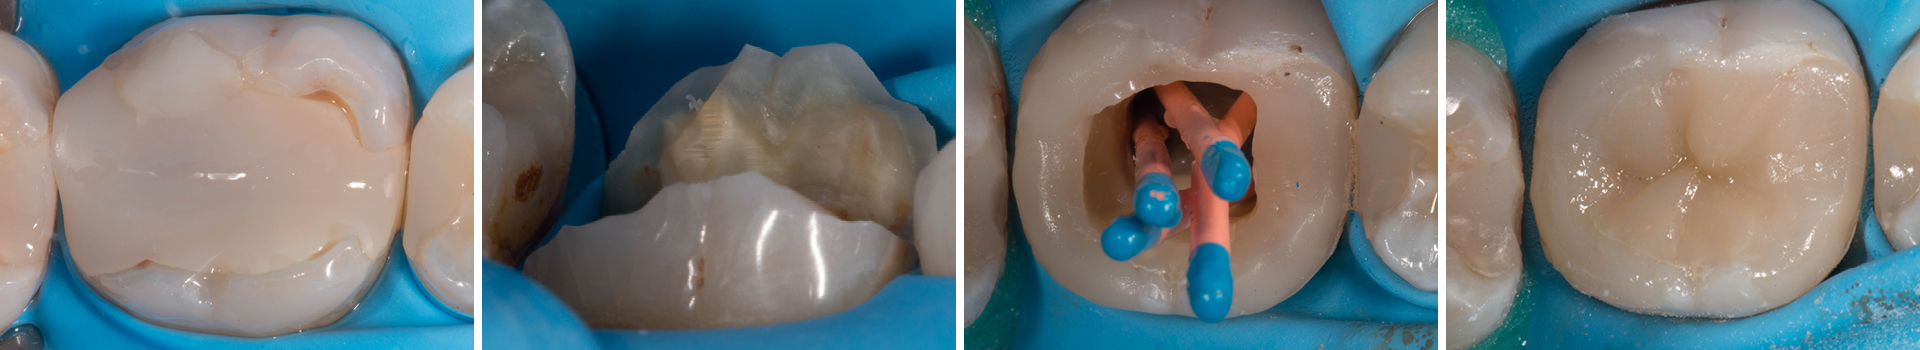

Abbildung 3

Initiale Zugangskavität: Mit einem Rosenbohrer wurde die alte Guttapercha reduziert. Für den Prä-Endo Aufbau wurden sowohl mesial als auch distal die Höcker partiell eingekürzt. Dies senkt das Frakturisiko bis zur indirekten Post-Endo Restauration.

Abbildung 4

Darstellung der partiellen Höckerreduktion von bukkal. Einkürzung um ungefähr 1,2 mm.

Abbildung 5

Für eine optimale Form des Approximalbereich wurden Matrizen und Holzkeile angelegt. Die Größe S sorgt für eine gute Position vom Kontaktpunkt. Da die Nachbarzähne noch restauriert werden, wurde hier auf einen Spannring verzichtet.